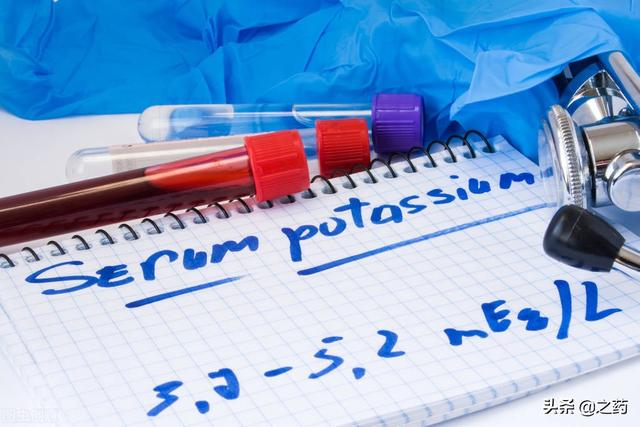

En clinique, la valeur normale du potassium dans le sang humain est de3,5 à 5,5mmol/L, une concentration de potassium dans le sang inférieure à 3,5 mmol/L correspond à un faible taux de potassium, c'est-à-dire à une concentration de potassium inférieure à 3,5 mmol/L."HypokaliémieLe syndrome d'hypersensibilité au potassium est considéré comme une carence en potassium. Elle est généralement due à la malnutrition, à un apport alimentaire insuffisant, à un épuisement dû à des tumeurs malignes, à des vomissements abondants, à des diarrhées d'une intensité incessante et à une étiologie fébrile.

Si vous présentez les symptômes ci-dessus, veuillez considérer qu'ils peuvent être causés par un faible taux de potassium dans le sang, nous vous recommandons de vous rendre à l'hôpital pour un test de potassium dans le sang, dans des circonstances normales, la concentration d'ions potassiumNe doit pas être inférieur à 3,5 mmol/lSi vous êtes en dessous de cette valeur, vous avez un problème de potassium dans le sang.

La concentration normale de potassium dans le sang est de 3,5 à 5,5 mmol/litre, et nous considérons généralement qu'un niveau inférieur à 3,5 mmol/litre est une hypokaliémie. Le corps d'un adulte moyen contient environ 150 grammes de potassium, qui est principalement stocké dans les cellules du corps.

En fait, il n'y a pas plus de deux raisons à l'hypokaliémie :Apports insuffisants en potassium和Excrétion excessive de potassiumLa concentration clinique normale de potassium est de 3,5 à 5,5 mmol/L, et le taux de potassium est de 1,5 à 1,5 mmol/L.Une valeur inférieure à 3,5 mmol/L est appelée hypokaliémie.。